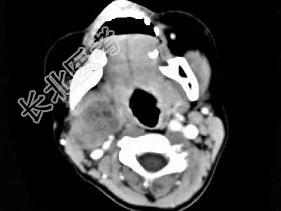

- 单项选择题女,4岁, 右侧颈部可扪及一包块约两个月,无热无痛, CT如图所示,最可能的诊断为 ( )

A、咽旁血管外皮瘤

B、咽旁副神经节瘤

C、咽旁脓肿

D、咽旁神经纤维瘤

E、咽旁小唾液腺混合瘤